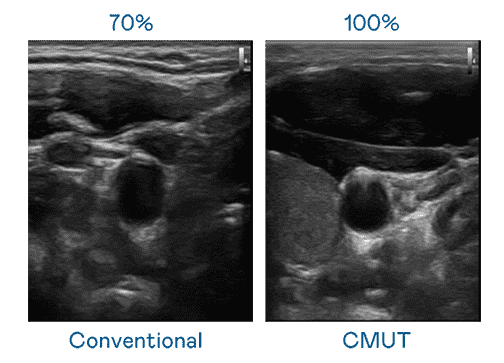

CMUT 技术是一种用电容式微机电元件来产生超音波讯号的技术。。与传统 PZT 压电式技术相比,,CMUT 频宽增加 30%,,,,更宽频的超音波讯号让影像解析度大幅提升,,,是实现高影像品质医疗超音波扫描、、、、促进精准医疗发展的关键技术。。。。

大频宽带来超清晰影像

超音波影像的解析度高低,,首先取决于探头能发出的讯号频宽。。尊龙集团 CMUT 可提供高清晰的超音波讯号,,,,提供高频宽、、高灵敏度、、影像纹理细节更高的超音波影像,,,,协助医护人员缩短影像判读时间及利用精准的医疗影像进行诊断。。。。